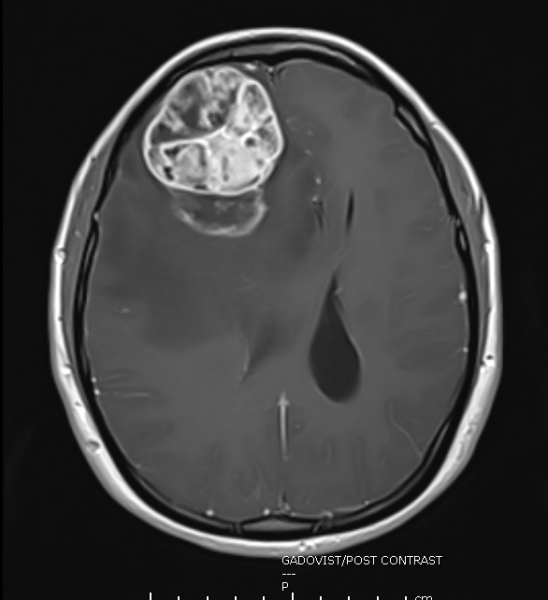

一开始小霞以为自己食物中毒,去急诊部挂号,做了断层扫描后,才发现有脑肿现象。脑部消肿后,再做磁力共振扫描,这才清楚看到右脑前方长了一颗网球般大的肿瘤,压迫右脑,造成善忘、头晕、头痛、精神散漫等问题。巨形肿瘤也造成右脑往左脑的方向推挤,导致脑水肿和颅内压增高。

长在右脑前方的巨大肿瘤,造成右脑往左脑推挤,导致脑水肿和颅内压增高。

化验报告出炉,证实是罕见的黏液样星形细胞瘤(Pilomyxoid astrocytoma),世界卫生组织对此肿瘤并没有分级,医学界认为它可能有较高的局部复发率,也可能蔓延至其他部位。